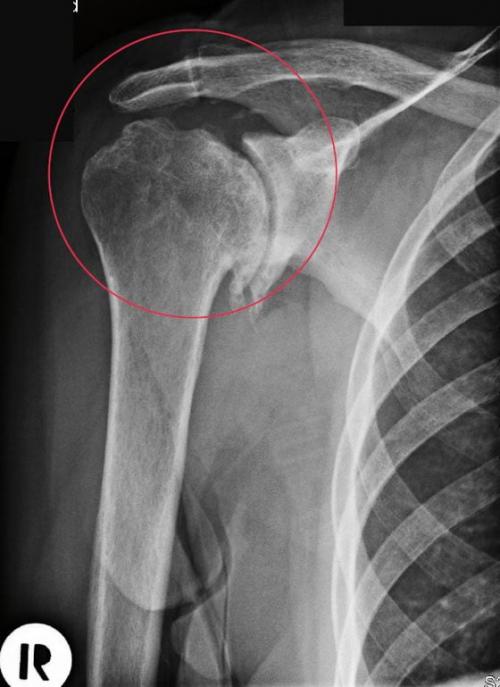

Диагноз на рентгене.

Головка плечевого сустава, пораженная артрозом.

Деформирующий артроз плечевого сустава 1 степени на рентгенограмме практически незаметен. Иногда удается установить небольшое сужение суставной щели. Однако при более серьезном обследовании – КТ или МРТ, поражение костно-хрящевой структуры четко заметно. Видны начальные деформации суставных поверхностей, отек подлежащих мягких тканей, небольшая узурация.

Деформирующий артроз плечевого сустава 2 степени проявляется уже значительными изменениями. Их можно представить так:

- резкое сужение суставной щели;

- деструкция суставных поверхностей;

- краевые остеофиты – костные разрастания;

- дефицит хрящевой прослойки;

- грубая узурация костных структур;

- остеопорозные изменения плечевой кости.

ДОА плечевого сустава 2 степени уже необратим, поэтому нужно стремиться к установлению диагноза именно на 1 стадии.